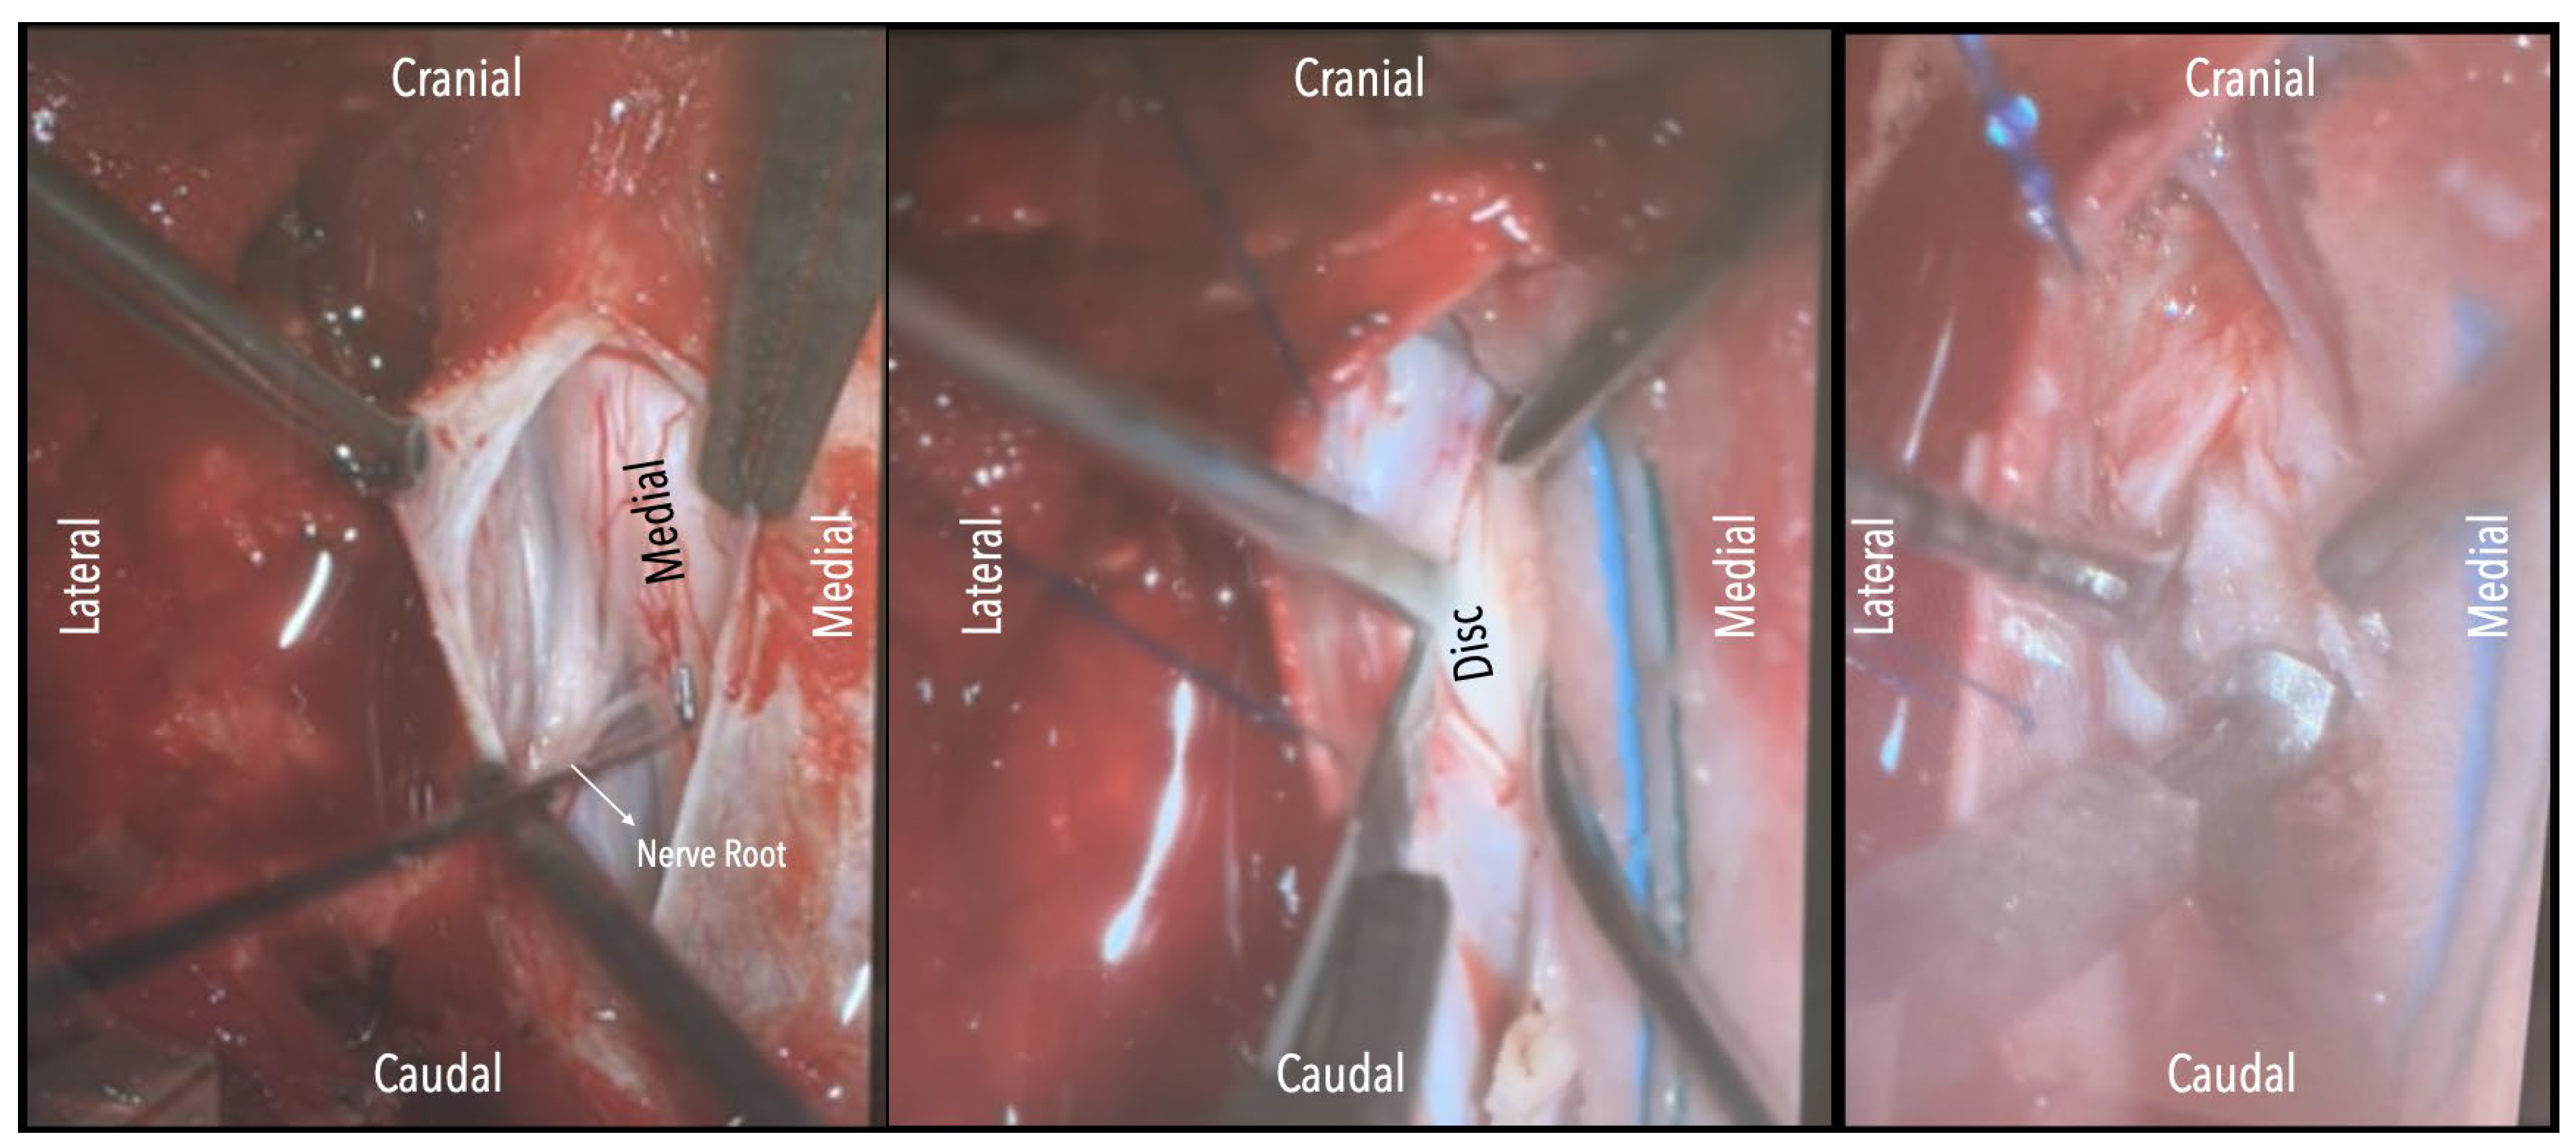

A wide en bloc laminectomy was performed at the disc level and one level above and below using a Misonix bone scalpel. This was followed by ipsilateral superior and inferior facetectomies and complete pediculectomy to establish an oblique and spacious working corridor toward the ventral spinal canal [Figure 1]. Under the operating microscope, the dura was opened in the midline with a no. 15 blade, and the arachnoid was incised sharply. CSF was allowed to drain passively for 10–15 minutes to reduce intradural pressure and promote relaxation of the spinal cord. The table was then tilted approximately 6–10 degrees to the contralateral side to allow for gravity-assisted displacement of the cord away from the operative field [Figures 2a,2b,3].

In three of the seven cases, the exiting nerve root at the level of the herniation was ligated due to poor visualization and transected extradurally to improve access. In the remaining four patients, the nerve root was either preserved or dissected intradurally using isocool bipolar diathermy and microsurgical scissors. With gentle medial retraction of the cord under gravity and protection using a micro-patty, the calcified disc was exposed. The ventral dura, when intact, was incised sharply and dissected from the disc surface where possible [Figures 2a,2b,3]. Disc removal was performed using a hockey-stick-shaped Misonix bone scalpel with constant irrigation, guided by intraoperative neuronavigation. The disc material was resected to a depth of 1–2 mm beyond the posterior vertebral wall to ensure adequate decompression. A second O-Arm spin was routinely performed following discectomy to confirm satisfactory decompression, especially given the limitations of the postoperative MRI due to the metal artefact [Figure 4, Figure 5 and Figure 6].

Figure 2a. Surgical field under microscope magnification. A: Opening of dura with no. 15 blade. B: Release of CSF. Following this, the table was tilted contralateral to the disc side to allow the cord (see annotation in image on the left) to slowly drift away. The dentate ligament, appearing as a thickening of the arachnoid, can be identified and dissected with microscissors. C: The nerve root is evident. If required, it could be sacrificed intramurally (see dashed line and annotation in image on the left side) with microscissors after being coagulated with bipolar diathermy.

Figure 2b. Intraoperative microscope view of the same case. Right-sided disc. A: The calcified disc is evident after gentle gravity-retraction of the cord. B: A hockey stick bone scalpel (MISONIX). C: Watertight closure of dorsal dura.

Figure 3. Intraoperative microscope view. Left-sided disc. Left: After opening the dura mater, the nerve root and cord are evident. Middle: Following drainage of CSF, dissection of the dentate ligament and gravity retraction, a micro-pattie is applied on the lateral aspect of the cord and a penfield microdissector is used to gently retract the cord, and the disc becomes evident. Right: Discectomy is carried out with a hockey stick bone scalpel.